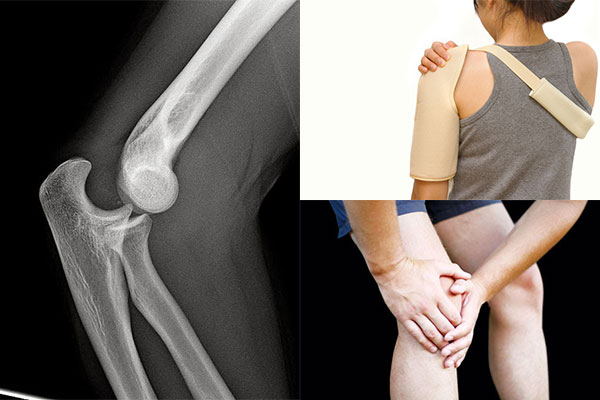

Chẩn đoán Sai khớp đầu xương quay hay Trật khớp khuỷu tay là Hỏi bệnh sử và khám thực thể. Việc chẩn đoán trật khớp sẽ được xác định bằng hình ảnh chụp X-quang. Ngoài ra có thể cần chụp cắt lớp vi tính (CT Scan) hoặc chụp cộng hưởng từ (MRI)

Điều trị Sai khớp đầu xương quay hay Trật khớp khuỷu tay nhằm đưa khuỷu tay trở lại vị trí bình thường. Điều trị trật khớp tùy thuộc vào vị trí và mức độ nặng của tổn thương. Bác sĩ có thể thử một số biện pháp nhẹ nhàng để đưa xương trở lại đúng vị trí. Sau đó khớp có thể được nẹp hoặc băng cố định trong vài tuần và bệnh nhân được dùng thuốc giảm đau hoặc thuốc giãn cơ. Trong một số trường hợp có thể phải phẫu thuật nếu có tổn thương mạch máu hoặc dây thần kinh hoặc nếu không thể nắn khớp về vị trí bình thường.